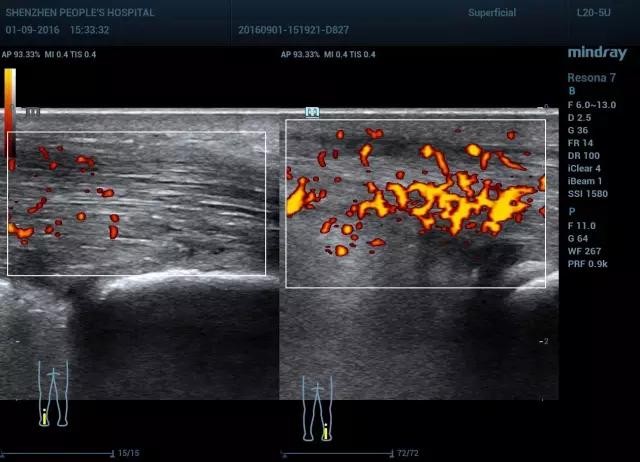

图11 腱周炎长轴血流双侧对比(图左 正常,图右 血流丰富)

图12 腱周炎短轴血流显示